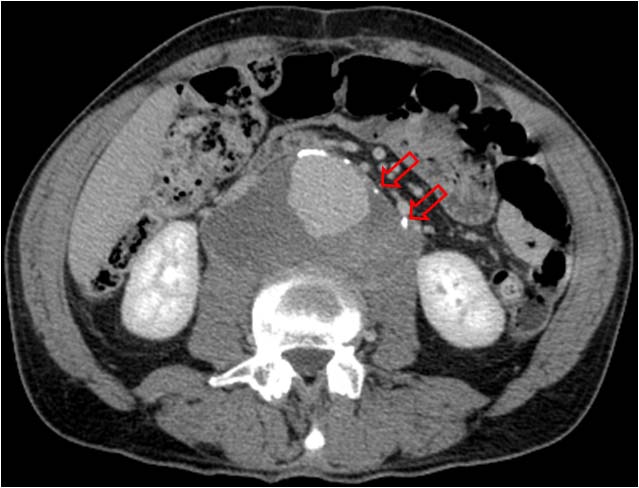

SIGNO DE LA AORTA PEQUEÑA

Signo de hipovolemia en la TC abdominal. Corresponde a vasoconstricción extrema de la aorta (flecha roja) como mecanismo que trata de compensar la hipovolemia que se ve en pacientes politraumatizados con grandes pérdidas hemáticas y en otras situaciones (shock séptico, cirugía, parada cardiaca, reacción alérgica,…). Se define como un calibre aórtico menor de 1,3 cm tanto dos centímetros por encima de las arterias renales como 2 cm por debajo. El ejemplo corresponde a un paciente politraumatizado con un bazo roto (flecha blanca).

Este signo forma parte del complejo de hipotensión en CT, antes llamado shock intestinal. Este término se refiere a un grupo de hallazgos abdominales en pacientes con hipotensión severa. Incluye: engrosamiento de asas de delgado (> 3 mm), realce de las paredes o hiperdensidad comparada con el psoas, vena cava inferior plana, aorta pequeña, heterogenicidad del páncreas con líquido peripancreático (no unánimemente aceptado), escaso realce del bazo (subjetivo), escaso realce hepático (25 UH menor que el bazo) e hiperrealce suprarrenal bilateral (hallazgo común en niños, controvertido en adultos).